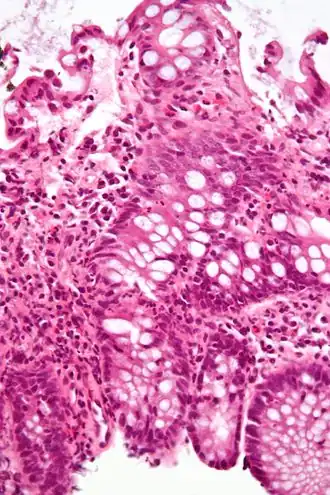

Une colite est une inflammation du côlon.